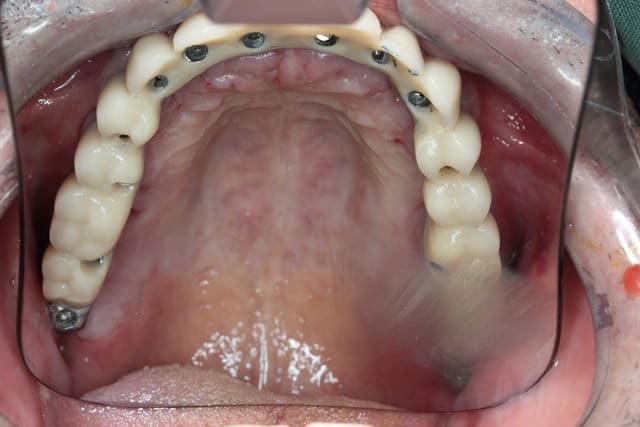

Vous vous dites sans doute que je ne vis plus ou que la chaleur m a empêché de continuer à poser des implants

Alors deux petites photos pour vous dire que je vais bien

Pour posit, les cylindres ont tous été posés à main levée et je pense que c est pas si mal que ça ;-)

Allez trois autre photos

La mandibule est faite

Ostéotension maxillaire en cours

Implanto maxillaire en nov 2013

Le scan pour vous faire patienter